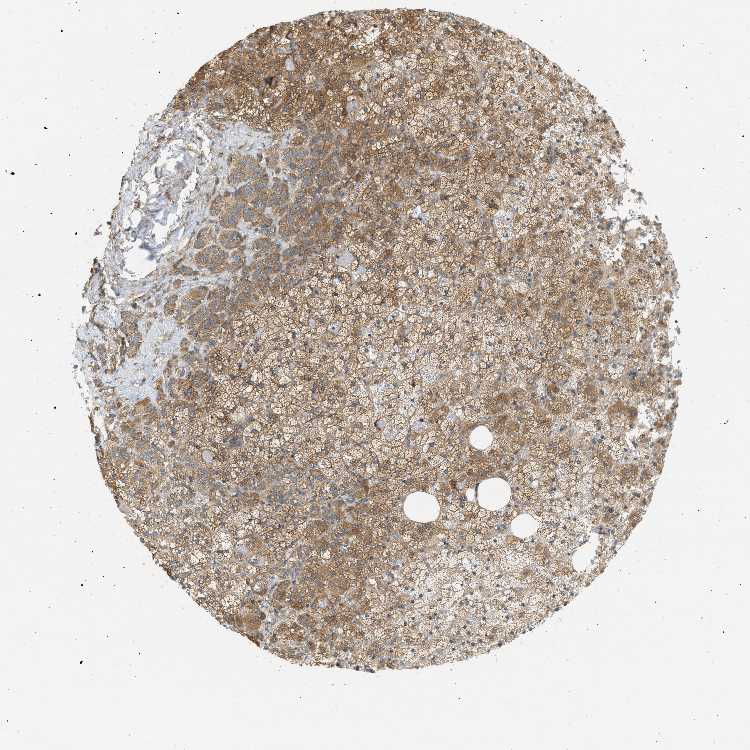

ADRENAL GLAND - Antibody stainingi

Antibody staining in the annotated cell types in the current human tissue is reported as not detected, low, medium, or high, based on conventional immunohistochemistry profiling in selected tissues. This score is based on the combination of the staining intensity and fraction of stained cells.

Each image is clickable and will lead to virtual microscopy that enables deeper exploration of all samples and also displays staining intensity scores, fraction scores and subcellular localization as well as patient and tissue information for each sample.

Antibody HPA017578

Glandular cells Medium